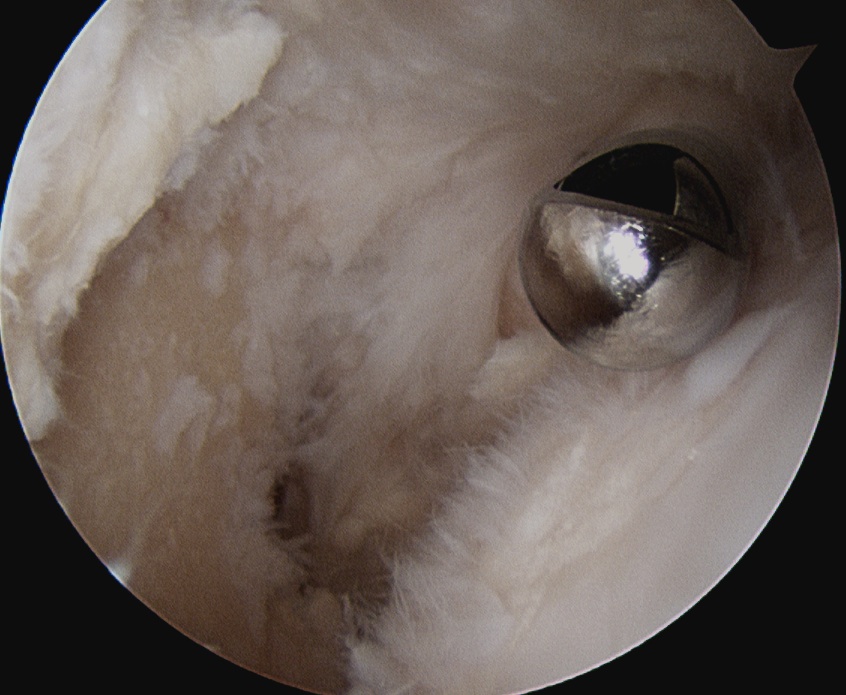

Arthroscopic Synovectomy

Kanbe et al. Eur J Orthop Surg Traumatol 2015

- arthroscopic synovectomy and capsular release for 54 RA shoulders

- mean follow up 5 years

- 67% receiving biologic treatments

- improvements in function and ROM